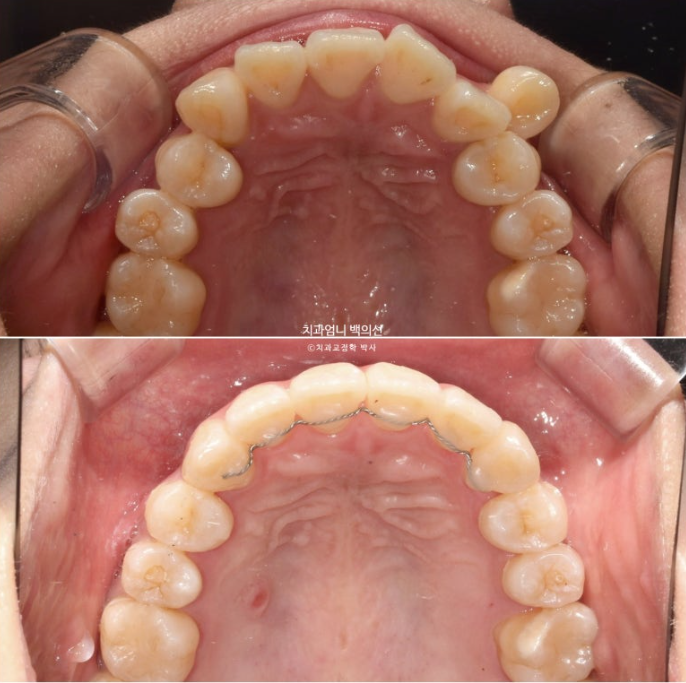

아래는 사랑니가 있던 공간으로 어금니를 뒤로 밀어내어 최종적으로 아래 앞니가 뒤로 2mm 들어가도록 했습니다.

위도 마찬가지로 사랑니 공간으로 어금니들을 전부 후방이동 시켜 덧니가 배열될 공간을 얻기로 했죠.

덧니가 배열되면서 자칫 주변치아들이 처음보다 뻗쳐나오지 않도록, 치료계획이 조금 복잡하더라도 신경을 많이 써야 합니다.

첫 세트의 장치는 66개가 나왔습니다.

재제작 추가장치 갯수는 17개 나왔습니다.

드디어 완벽히 일치하는 치아 중심선과 안정적인 덧니 배열

치아중심선은 위 아래 치아끼리 맞는 것도 중요하지만, 전반적인 인중과 얼굴과도 맞아야 합니다.

어금니 교합이 좋지 않으면 치료를 마무리 짓지 않습니다.